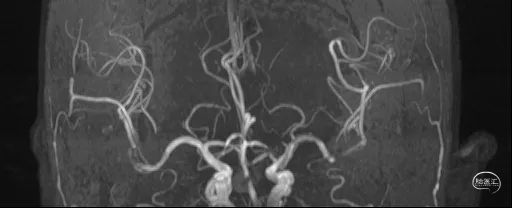

全脑血管造影DSA:双侧椎动脉起始段狭窄。远端供血不足。

患者双侧椎动脉均狭窄,左侧重度狭窄。左侧椎动脉充盈延迟、血流瘀滞,为闭塞前表现。所以权衡双侧椎动脉狭窄血管成型术的指征,优先处理左侧椎动脉起始段狭窄。为预防急性后循环缺血性卒中,在家属知情同意前提下行支架成形术。